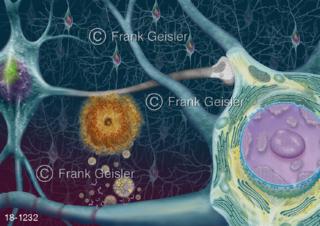

18-1232 Nerven Hirnrinde Gehirn mit Amyoloid-Plaques bei Alzheimer-Krankheit Demenz